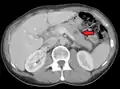

Initially, nearby lymph nodes are struck early.[9] The lungs, liver, brain, and bones are the most common metastasis locations from solid tumors.[9]

Metastatic tumors are very common in the late stages of cancer. The spread of metastasis may occur via the blood or the lymphatics or through both routes. The most common sites of metastases are the lungs, liver, brain, and the bones.[10]